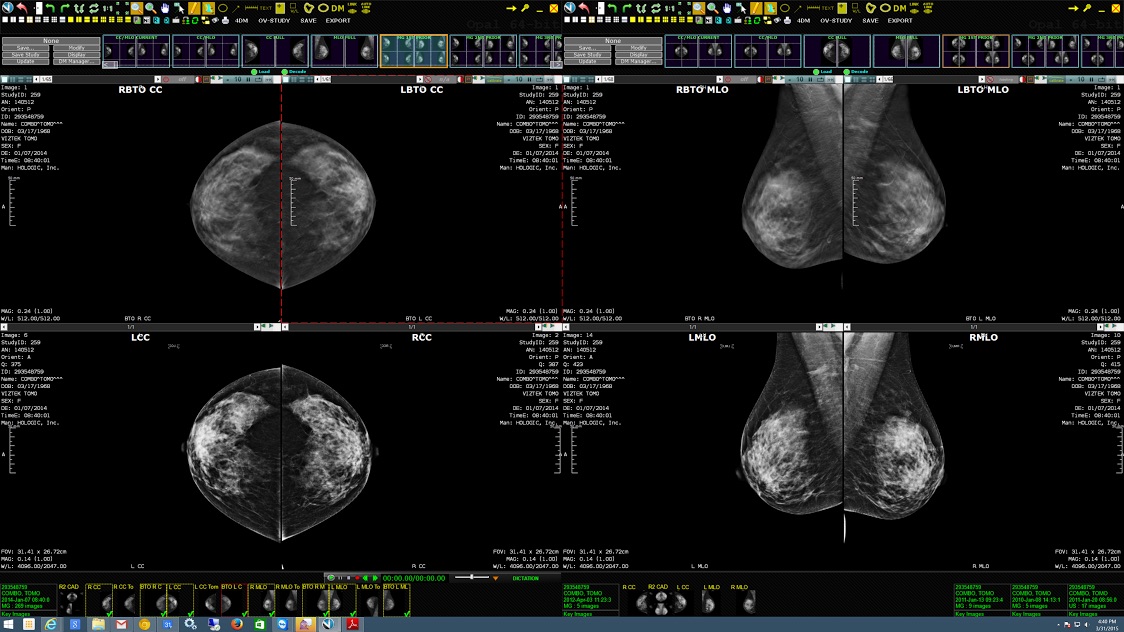

Breast Imaging: 4th edition | Bonnie N. Joe | ISBN。Radiology–pathology correlation of hormonal subtypes of。Breast Imaging (The Core Requisites): 9780323051989。マンモグラフィーや超音波などの診断技術を網羅した、拡大改訂版の医学書。。41mYn2qddfL._AC_SY200_QL15_.jpg。- 書籍名: Diagnostic Breast Imaging- 著者: Sylvia H. Hewayng-Köbrunner, D. David Dershaw, Ingrid Scherer- 版: 第2版, 拡大改訂版- 出版社: Thieme- 内容: マンモグラフィー、超音波、磁気共鳴画像、介入手技に関する情報ご覧いただきありがとうございます。ジュンケイラ組織学 第5版 (原著第14版)